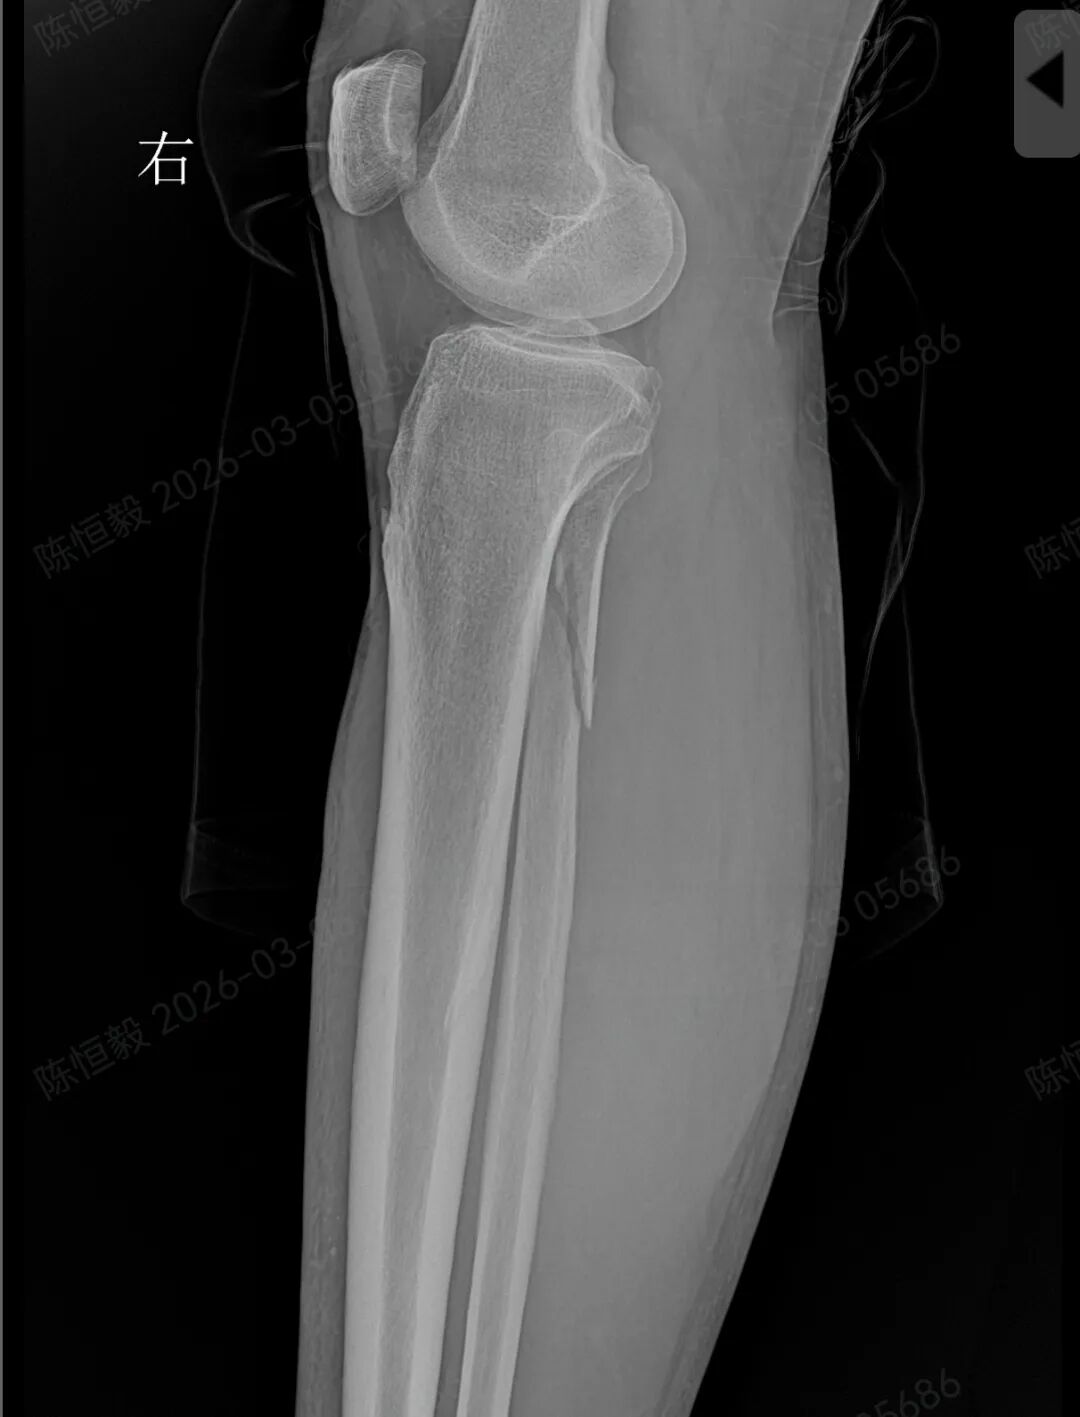

王大爷听从建议住院后,经完善体格检查及 CT 检查,最终确诊为复杂的 Maisonneuve 骨折:不仅存在下胫腓分离,还合并前踝 Chapute 结节撕脱骨折、后踝骨折、内踝骨折,同时伴有腓骨高位骨折。

这类联合损伤必须通过手术治疗,若延误干预,后续极易引发创伤性关节炎、踝关节不稳定,严重影响正常行走功能。

普通 X 光片仅能判断是否存在明显骨折、脱位,对于下胫腓联合损伤、微小骨折、软骨损伤,以及 Maisonneuve 骨折涉及的腓骨高位骨折等隐匿性损伤,很难清晰显示。